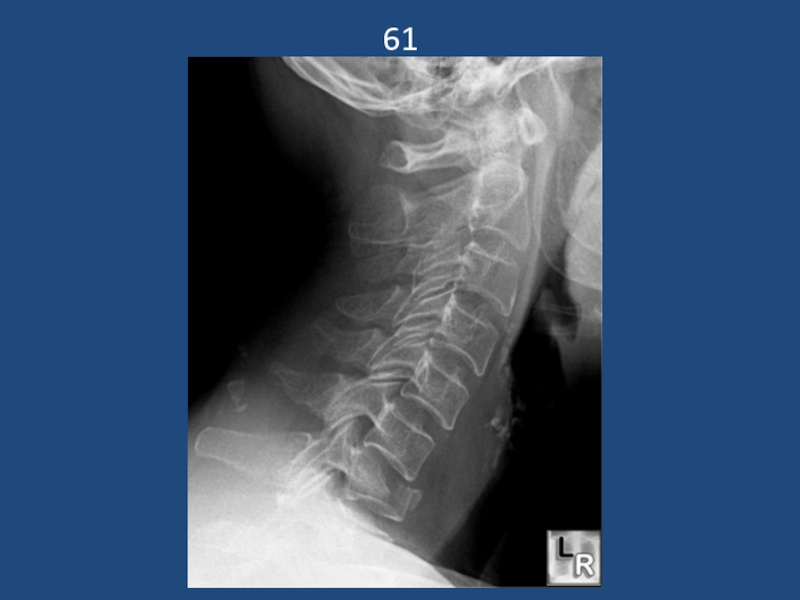

Подвывих с3 кпереди. Взрывной перелом с6

Слайд 1514

перелом основания зуба с захватом телас2.